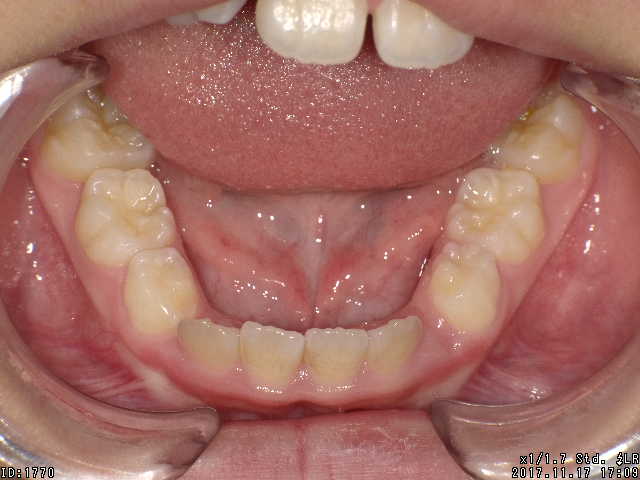

矯正後

| 通院目的 | 永久歯を抜かずに歯並びを治したい。 |

| 処置内容 | プレート拡大処置・ディスタライザー・インビザライン・オーソテイン・マルチブラケット装置 |

| デメリット・院長コメント | 永久歯を抜かない治療のデメリットは、治療期間が長いことです。 ただし、その後の人生の長さを考えると、健全な小臼歯を2本または4本抜歯の矯正治療よりも、はるかにメリットがあるといえます。 また、アーチが小さくならないので、舌が後ろに押し込まれないためいびき防止につながり睡眠の質の向上にもつながります。 |